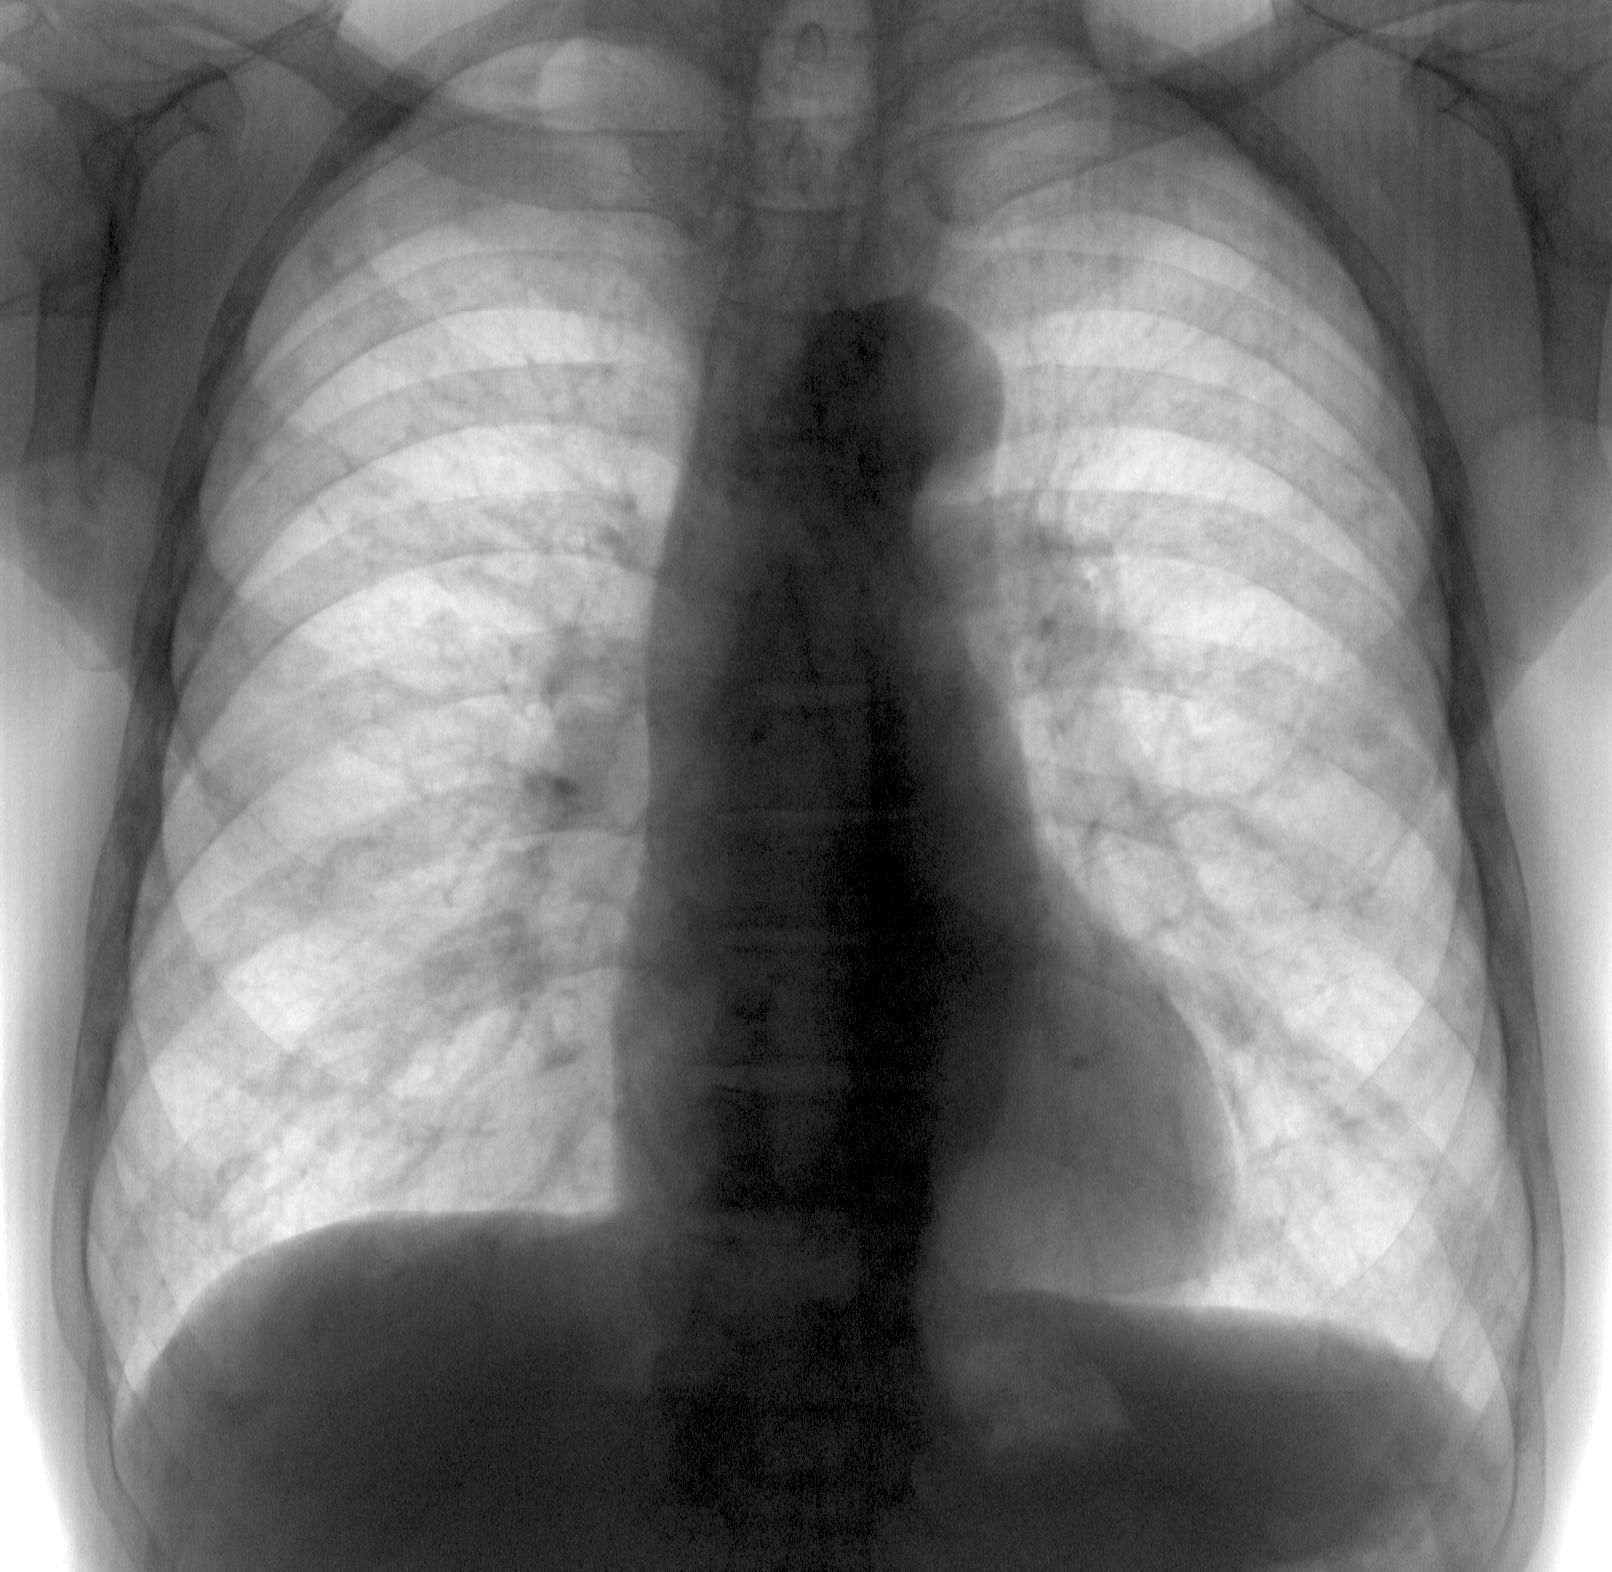

Трехлетняя динамика. Вторая флюшка сегодняшняя. Жалоб на легкиене не предьявляет, кроме аденомы простаты - никаких проблем. Отправил в онко. Но глаз упал на нижние углы лопаток. Там то же, что и в легких?

Лимфоузлы скорее всего кальцинированные. В лёгких расценил, как канцероматозную дессиминацию.

Могу предположить опухоль в желудке. Пускай покритикуют

Такое ощущение, что все это в ребрах, не в легких.

А как на счет углов лопаток? Или это все кааца? А если нет, то возможно это и в ребрах?

А может миеломная ?

При метастазах и миеломной должна быть потеря костной массы, а тут наоборот более интенсивные тени очагов. На бластические тоже не похоже, я думаю, оно в легких

очаги лежат вне ребер, в легких!

Невнятно выразила свою мысль, имела в виду костное метастазирование, в ребра и лопатки, Ola-la права.

костное метастазирование, в ребра и лопатки, Ola-la права.

Мне видятся метастазы и в легких, и в костях. Рак простаты так себя ведёт.Да собственно, не только он. Пересмотреть надо "аденому"